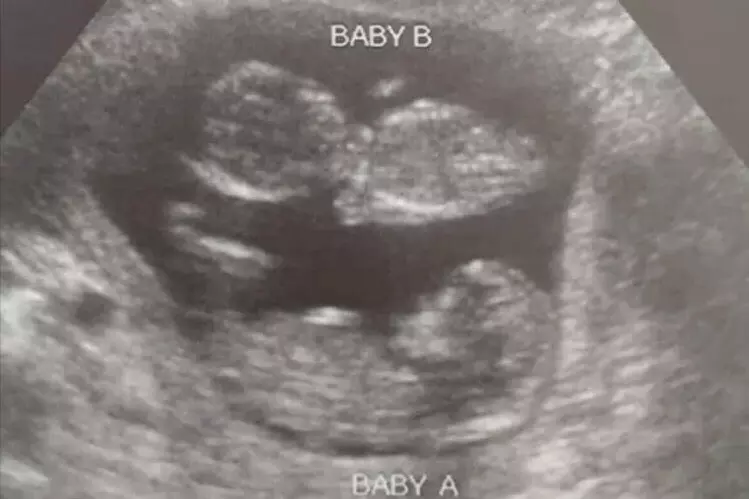

In a Facebook post made this week, Boles shared the following, along with a glowing picture of the unborn twins:

Problem #2: they didn’t tell her that she was having twins. Either their sonographer was incompetent, or they once again lied since they know that a woman who finds out that she’s having twins may have a harder time with the thought of aborting two babies instead of one.

Problem#3: and this really isn’t a problem - at least not for us. The abortion pill didn’t work. The patient is now very happy that it didn’t work. Why didn’t it work? Probably because the extra progesterone from the fact that there are two babies overcame the progesterone blockade that the abortion pill tries to create.

Today, [the patient]’s more than 12 weeks and is very happy. Both babies, and mom as well, are going to be fine.